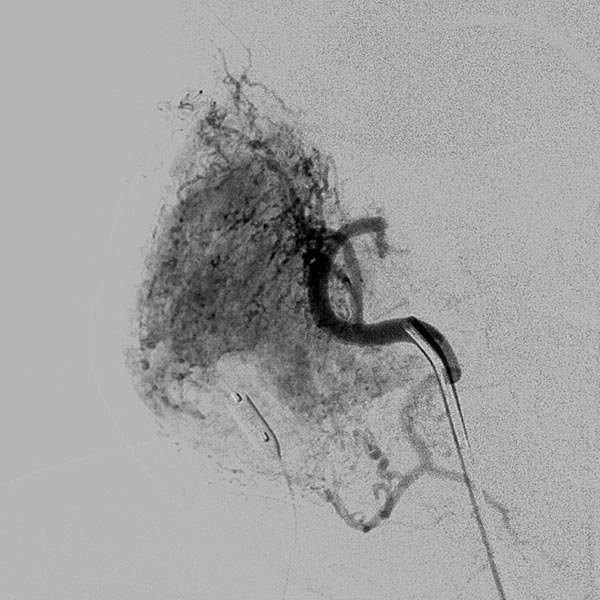

Digitale Subtraktionsangiographie (DSA): Nach Einbringen transarteriell eines Führungskatheters 4F in die Arteria carotis externa und Vorbringen eines Mikrokatheters in die Arteria maxillaris. Das Hämangiom zeigt sich als typisches KM-Pooling (Tumorblush). Gut zu sehen auch der transvenös eingebrachte Ballon, der den venösen Abstrom ausblockt. Hier wird jetzt mit Partikeln der Größe 150 Mikron embolisiert ohne dass diese Partikel venös abströmen können.

Digitale Subtraktionsangiographie (DSA) nach erster Embolisation mit Partikeln. Ein Teil des Hämangioms ist schon ausgeschaltet.

Digitale Subtraktionsangiographie (DSA) nach erneuter superselektiver Embolisation mit Partikeln über einen Mikrokatheter unter Blockung des Abstroms. Es sind jetzt gut 50 % des Hämangioms erfolgreich embolisiert.